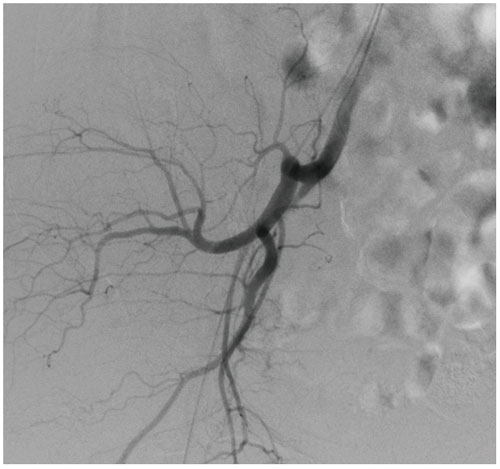

DSA is used to clearly visualize blood vessels in a

bony or dense soft tissue environment. Images are produced using contrast medium by subtracting a “pre-contrast image” or mask image from subsequent images, once the contrast medium has been introduced into a structure.